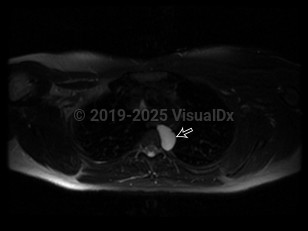

Bronchogenic cyst in Adult

A bronchogenic cyst is a congenital respiratory tract malformation arising as an embryonic out-pouching of the foregut or trachea. Bronchogenic cysts can be found anywhere along the tracheobronchial tree and are often asymptomatic unless they become infected. Cysts typically appear as sharply marginated, water-density lesions on chest x-ray and may contain air-fluid levels when infected.